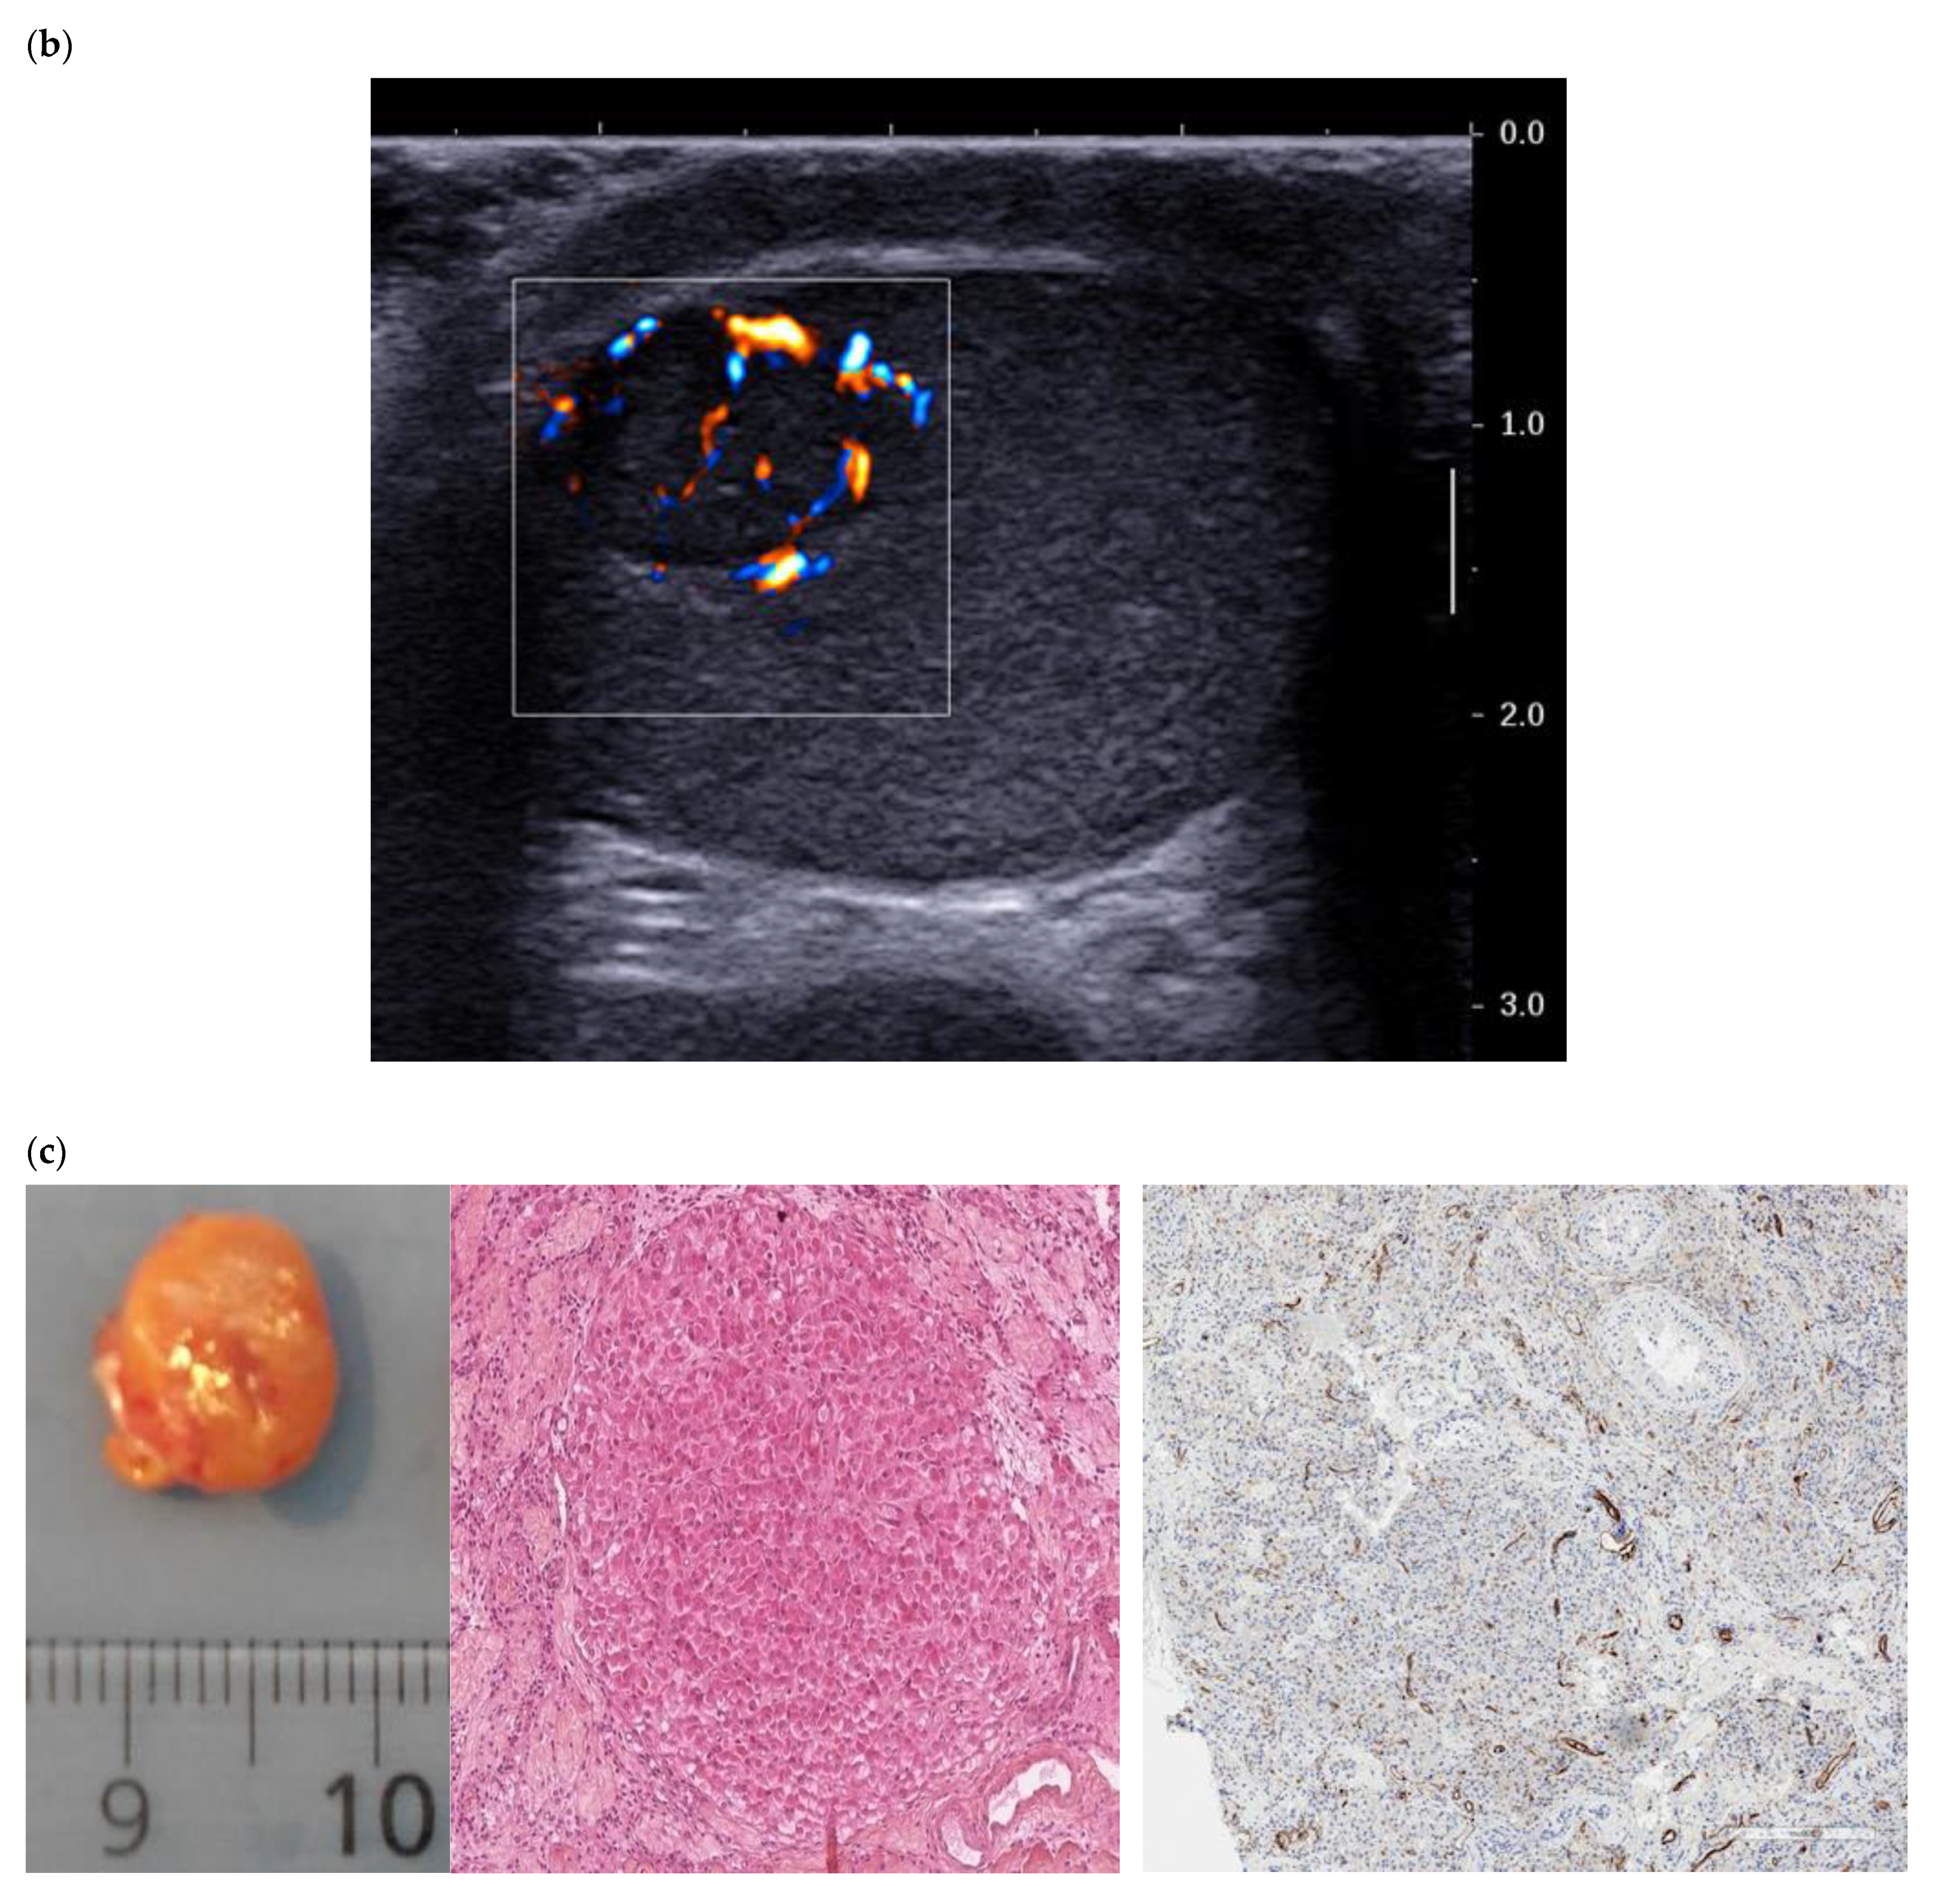

These differences can be explained by improvements in the sensitivity of ultrasound probes and in the performance of the Doppler mode. The use of ultrasensitive Doppler further improves the detection of intra- and peri-lesional flows and ameliorates identification of the enveloping pattern, which is suggestive of LCTs (Figure 2) [16].

Figure 2.

(a) Same lesion as Figure 1 with ultrasensitive Doppler allowing better characterization of corbelling vascular architecture. (b) Small LCT of 7 mm, marked hyper vascularization compared with adjacent pulp, with main feeding vessel pattern.

This tool can also help to differentiate predominantly peripheral vascular architecture from radial trans-lesional vascularization, which seems to be more indicative of seminoma (Figure 3) [14].

Figure 3.

(a) Typical LCT 16 × 14 mm with mixed corbelling and central vascularization pattern in a 42-year-old patient presenting for infertility work up. The large size of the lesion helps to highlight this typical pattern. (b) 31-year-old patient presenting for right testicular mass: 38 mm typical seminoma with a radial trans-lesional « anarchic » vascularization pattern.